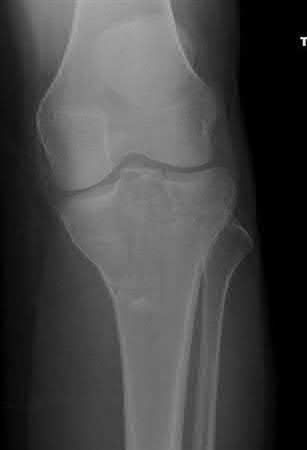

Figure B demonstrates an isolated medial femoral condyle fracture. Lateral locked plating is not an appropriate technique for this fracture.

The fracture shown in Figure B is an AO B type (partial articular fracture). This fracture is best treated with open reduction internal fixation through a medial approach, with lag screw and buttress plate fixation.

Figures A, C, D and E show supracondylar distal femur fractures that can be treated with ORIF with a fixed-angle device such as lateral locked plating.